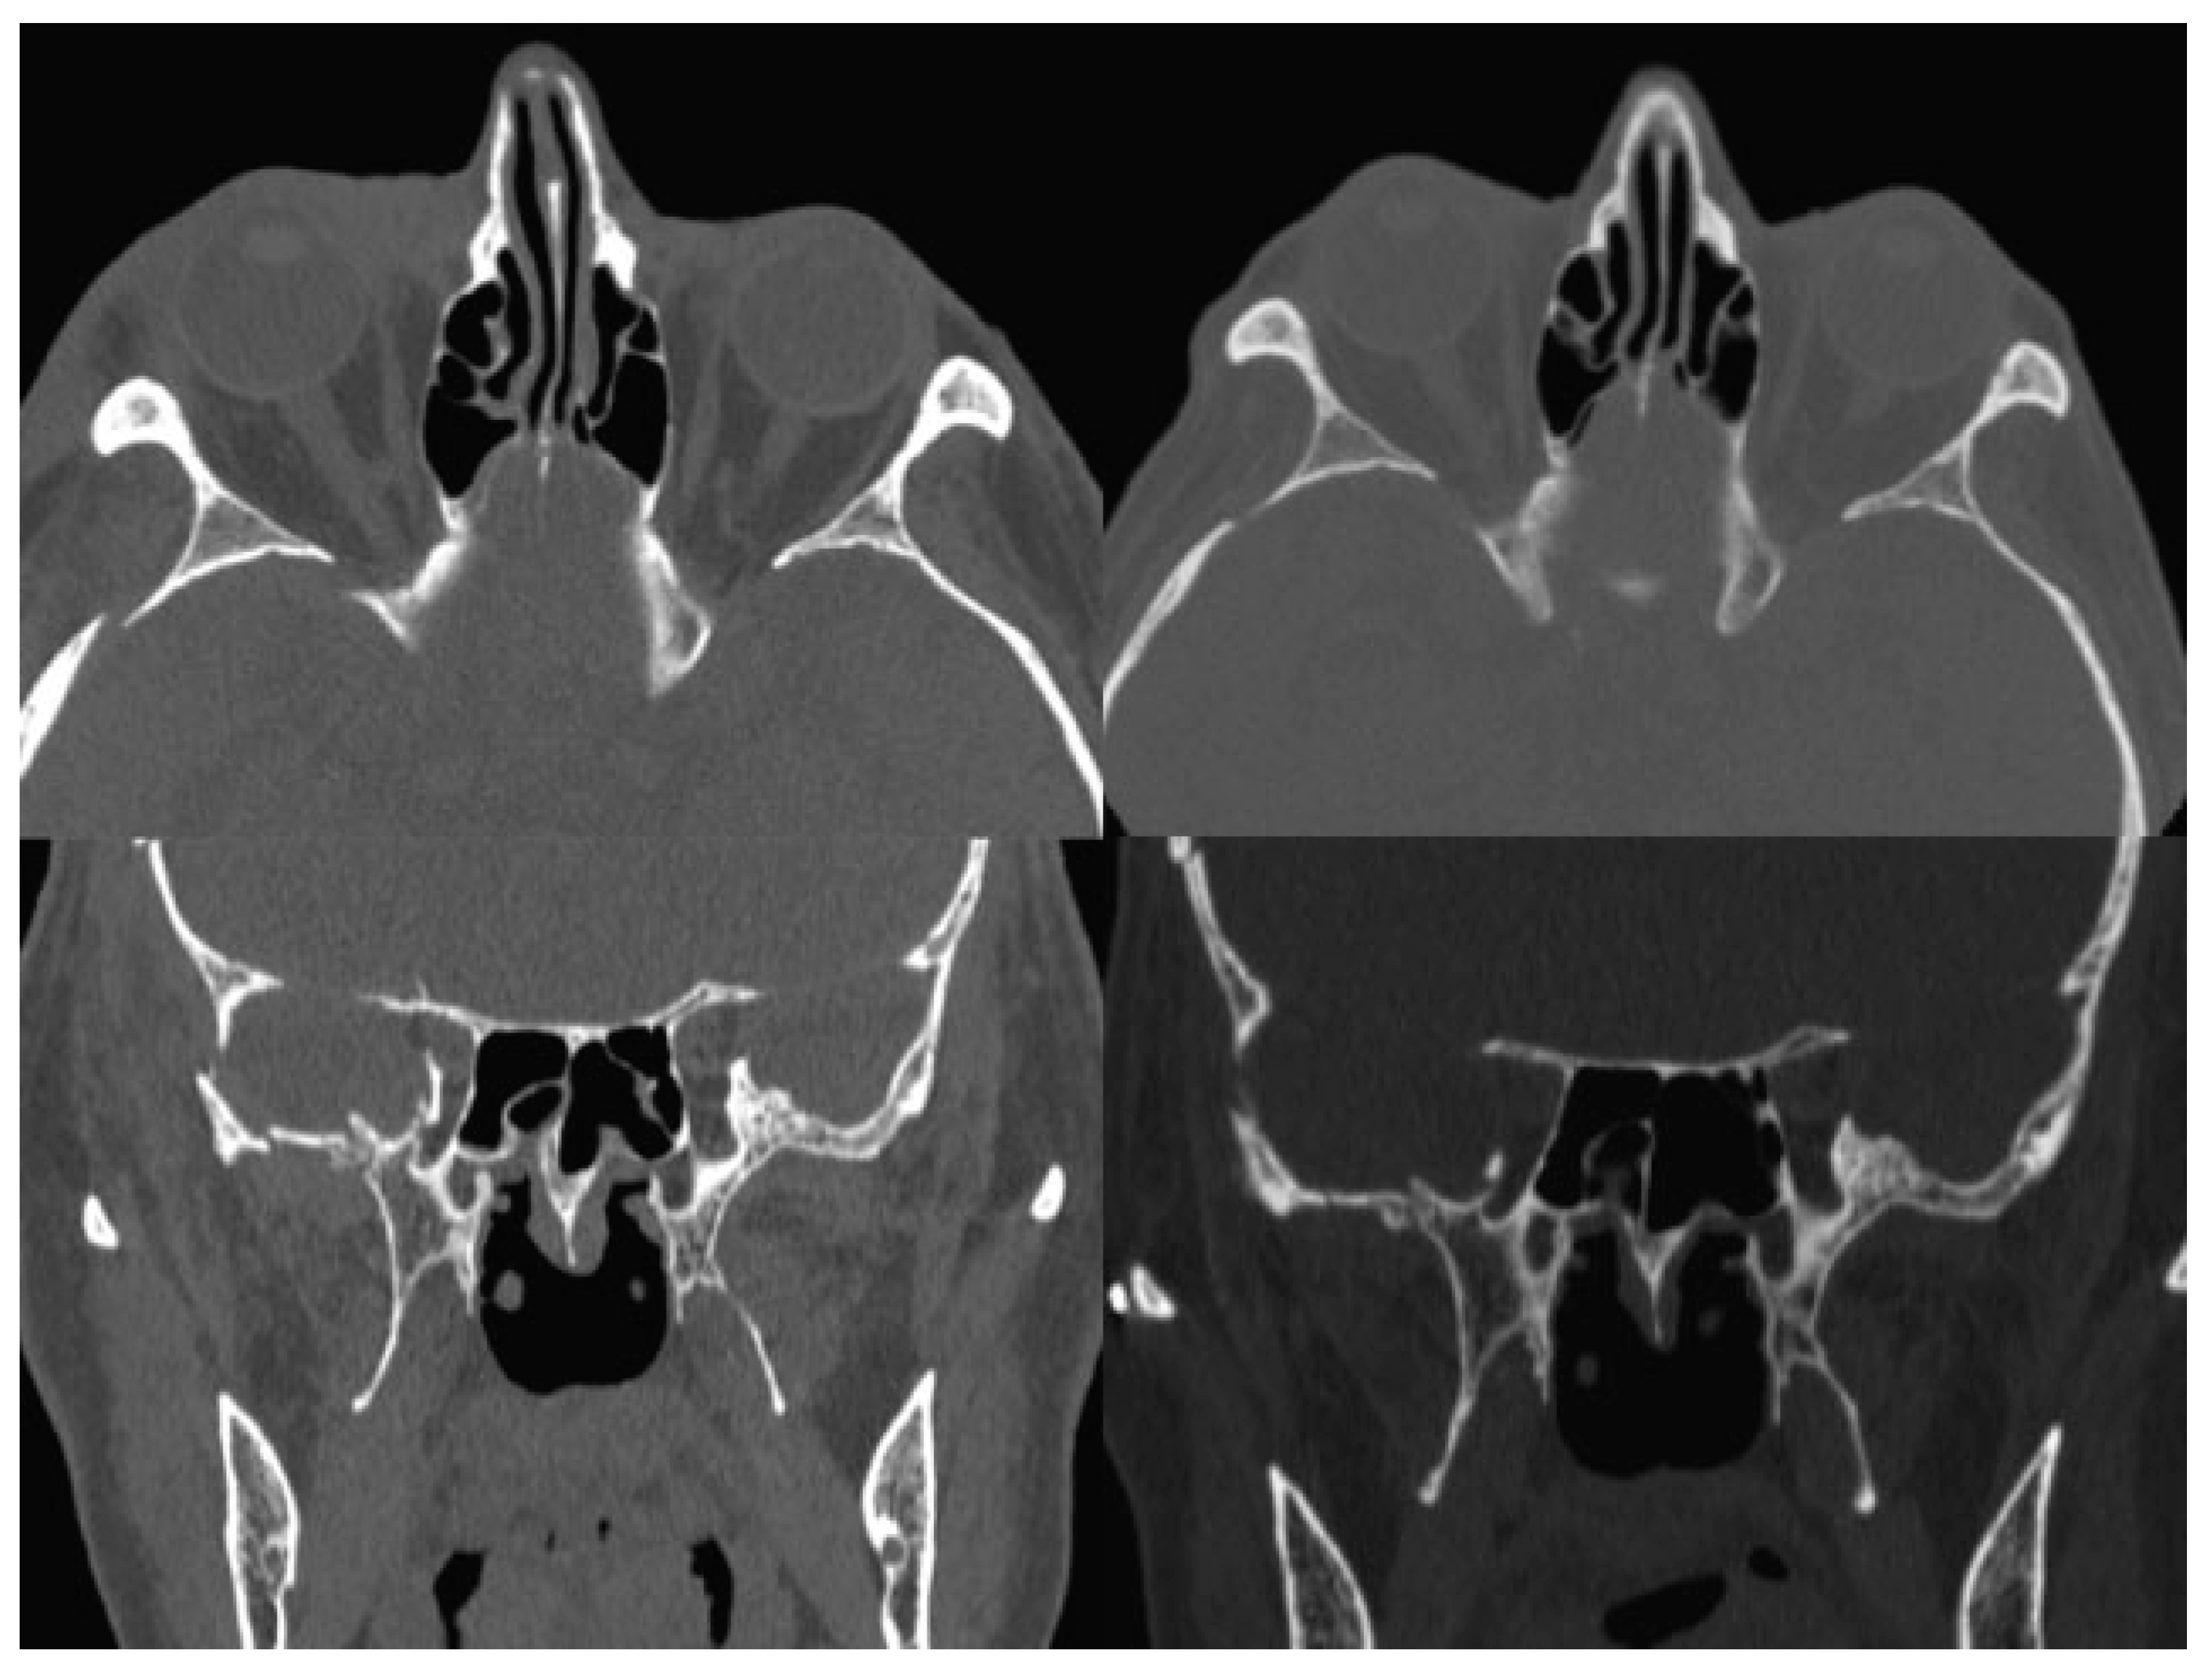

The postsurgical CT scan revealed a full recovery of the right SOF size (Figure 4). One week postoperatively, physical examination showed a great improvement of all symptoms, a prompt and almost complete recovery of the abducens movement, without diplopia (Figure 1). In 1 month, the patient completely healed.

Figure 4.

Left: Axial and coronal preoperative CT scan: note SOF size reduction; right: Axial and coronal postoperative CT scan: note SOF size recovery. CT, computed tomography; SOF, superior orbital fissure.